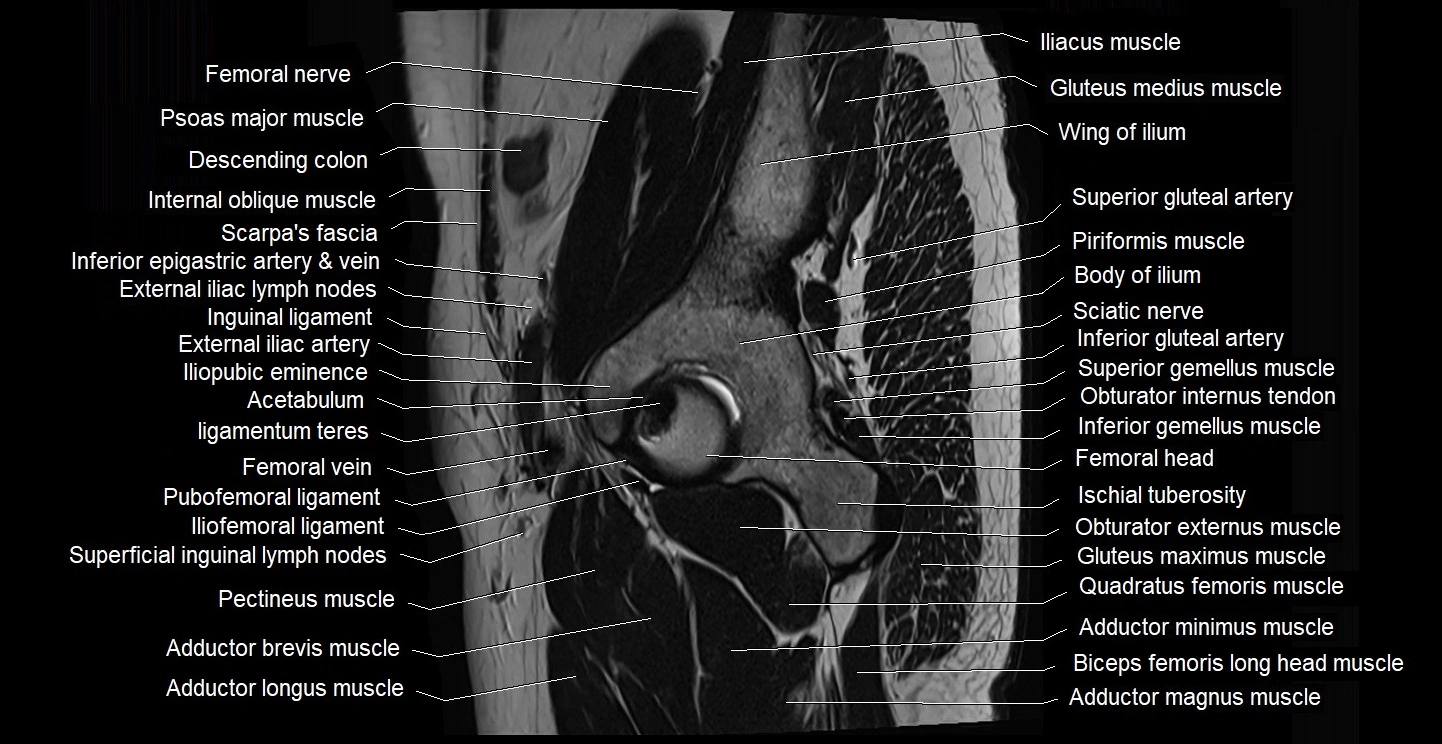

- Acetabulum

- Adductor brevis muscle

- Adductor longus muscle

- Adductor magnus muscle

- Adductor minimus muscle

- Body of ilium

- External iliac artery

- External iliac lymph nodes

- External iliac vein

- Femoral artery

- Femoral nerve

- Femoral vein

- Gluteus maximus muscle

- Gluteus medius muscle

- Head of femur

- Iliofemoral ligament

- Iliohypogastric nerve

- Iliopsoas muscle

- Iliopubic eminence

- Inferior gemellus muscle

- Inferior gluteal artery

- Inguinal ligament

- Inguinal lymph nodes

- Ischial tuberosity

- Ligamentum teres (ligament of the head of femur)

- Obturator externus muscle

- Obturator internus muscle

- Obturator internus tendon

- Pectineus muscle

- Piriformis muscle

- Psoas major muscle

- Pubofemoral ligament

- Quadratus femoris muscle

- Sartorius muscle

- Sciatic nerve

- Superficial inguinal lymph nodes

- Superior gemellus muscle

- Superior gluteal artery